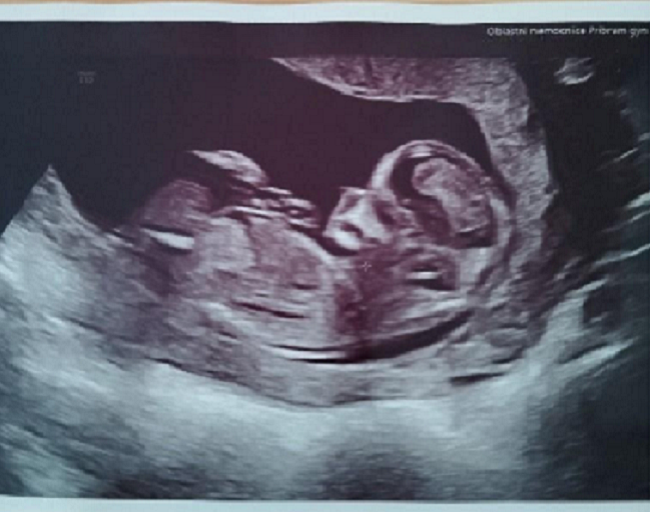

Přinášíme vám oblíbený seriál, ve kterém budeme sledovat náročné těhotenství maminky Katky doslova v přímém přenosu. Maminka Katka se s vámi podělí o své pocity, nálady, události aktuálních týdnů těhotenství. Nebudou chybět ani těhotenská vyšetření. Včetně jedinečného pohledu Katky na jejich rodinu, rodičovství jako partnerství a speciálně popíše i pohled chlapa na rodičovství. Tentokrát se máte opět na co těšit!